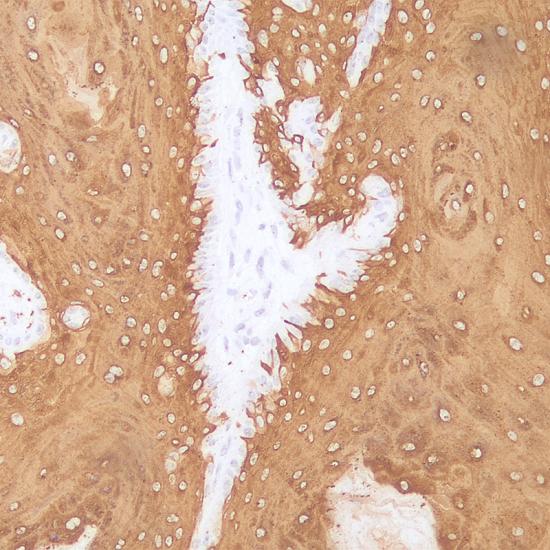

細(xì)胞角蛋白CK10分子量為56.5kDa,主要標(biāo)記上皮的基底上皮和顆粒細(xì)胞層,同時(shí)CK10的表達(dá)與細(xì)胞的分化程度呈正比,高分化者呈陽性,主要用于鱗癌的診斷。